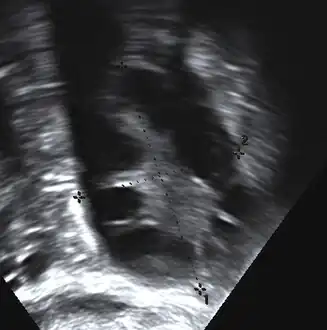

A polycystic ovary

The syndrome acquired its most widely used name due to the common sign on ultrasound examination of multiple (poly) ovarian cysts. These "cysts" are in fact immature ovarian follicles. The follicles have developed from primordial follicles, but this development has stopped ("arrested") at an early stage, due to the disturbed ovarian function. The follicles may be oriented along the ovarian periphery, appearing as a 'string of pearls' on ultrasound examination.[86]

• Gynecologic ultrasonography, specifically looking for small ovarian follicles. These are believed to be the result of disturbed ovarian function with failed ovulation, reflected by the infrequent or absent menstruation that is typical of the condition. In a normal menstrual cycle, one egg is released from a dominant follicle – in essence, a cyst that bursts to release the egg. After ovulation, the follicle remnant is transformed into a progesterone-producing corpus luteum, which shrinks and disappears after approximately 12–14 days. In PCOS, there is a so-called "follicular arrest"; i.e., several follicles develop to a size of 5–7 mm, but not further. No single follicle reaches the preovulatory size (16 mm or more). According to the Rotterdam criteria, which are widely used for diagnosis of PCOS,[10] 12 or more small follicles should be seen in a suspect ovary on ultrasound examination.[21] More recent research suggests that there should be at least 25 follicles in an ovary to designate it as having polycystic ovarian morphology (PCOM) in women aged 18–35 years.[95] The follicles may be oriented in the periphery, giving the appearance of a 'string of pearls'.[96] If a high-resolution transvaginal ultrasonography machine is not available, an ovarian volume of at least 10 ml is regarded as an acceptable definition of having polycystic ovarian morphology. rather than follicle count.[95]